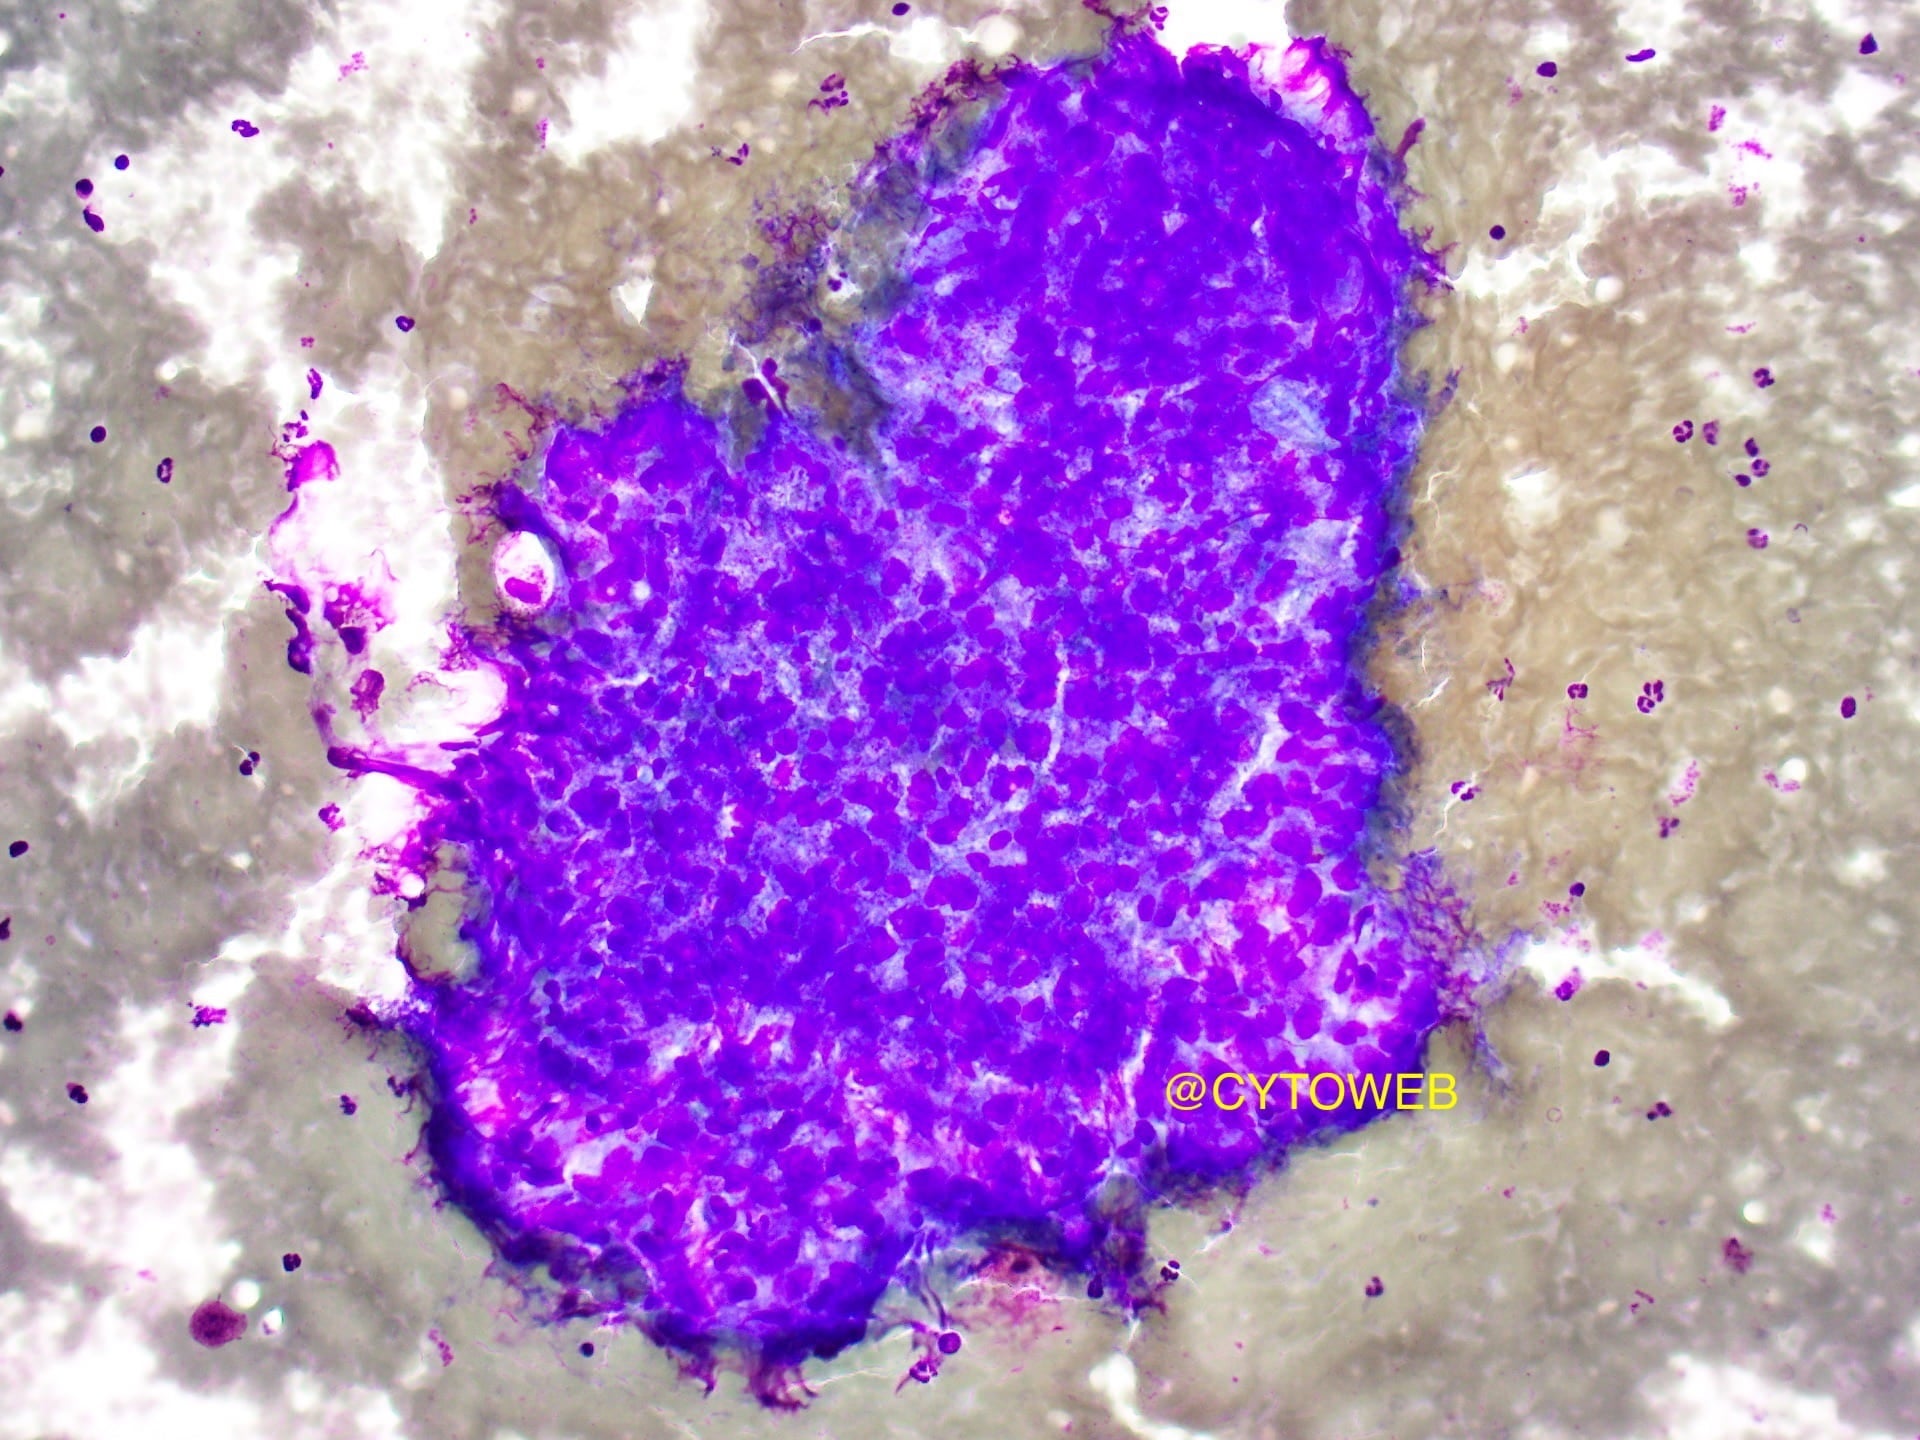

- Crowded sheets of tumour cells with overlapping nuclei

- Acinar formation is discernible within the sheets

- Moderate to abundant pale cytoplasm

- Clean background – no necrosis